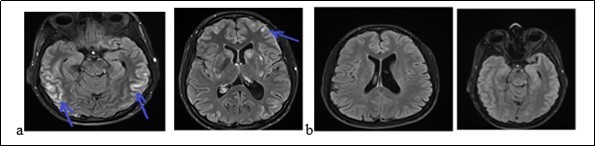

A 31-year-old pregnant woman was admitted to hospital because of headaches, vomiting and rotational dizziness on December 29, 2017. A series of headache followed by vomiting and dizziness began at 33 weeks of pregnancy (a month before her admission). We noticed that the blood pressure reached 150 / 90mmHg. She was treated with oral nicardipine for one month. The delivery took place without postpartum complications. She had been treated with bromocriptine for breast congestion. Three days after delivery, she had thunderclap posterior headache, nausea chills with asthenia without fever, polyuria and polydipsia. The manifestation of the headache was 9.5 / 10 on the Visual analogical Scale. In her medical history, she underwent a surgery of an ovarian cyst and a left temporal arachnoid cyst in 2007. She is an active smoker at 15 boxes-years. The neurological and other physical examinations were normal. The routine biological, metabolic, infectious and immunological check-up was normal. The MRI had displayed a subarachnoid hemorrhage associated with hypersignals on Flair sequences of bilateral hemispherical cortex, on the central gray nuclei and the cerebellar hemispheres. The Angiography had not shown any stenosis. The MRI (Figure 3) had displayed on diffusion sequences, two punctiform infarction of right putamen and caudate nuclei. The apparent diffusion coefficient was high for the other bi-frontal lesions. All these findings led us to conlude with RPE syndrome complicated by subarachnoid hemorrhage and cerebral ischemia. The patient had been treated with decreasing dose of nimodipine for three months. At 6 weeks of progress, the neurological examination was normal. The Brain MRI (Figure 3b) displayed a complete decrease of the flair hyper signals from the basal ganglia and the cortex. The outcome was good.

Figure 3.The brain MRI with flair sequences showing bi-temporal and frontal hyper signals (a) and a complete decrease of lesions after treatment (b).